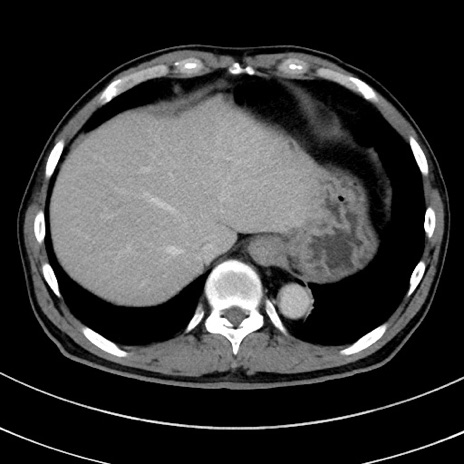

冠状断像

【症例】 60歳代男性

【主訴】 黒色吐物

【現病歴】 4日前から嘔気自覚、2日前の朝食後にも嘔気あり、自分で手で嘔吐反射起こし嘔吐したところ血が混ざっていたため受診。

【既往歴】 5年前汎発性腹膜炎を伴う急性虫垂炎で手術、高血圧、前立腺肥大症、高脂血症

【身体所見】 腹部正中に手術癩痕あり 腹部平坦・軟圧痛なし膨満感あり

【データ】WBC 8400、CRP 4.54